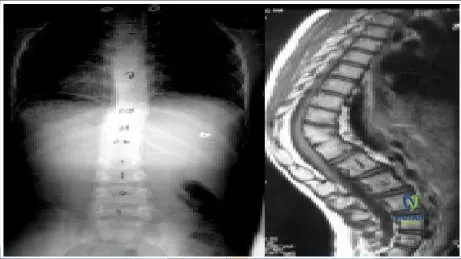

The distance between the apical thoracic pedicle and the thecal sac is less than 1 mm on the concave side.

The aorta is on the left side of the vertebra in the upper and midthoracic spine. The aorta moves to an anterior location in the lower thoracic spine. The distance from the aorta to the vertebral body is 6 mm to 7 mm in skeletally mature patients with idiopathic scoliosis between the fourth and ninth vertebral bodies. The distance becomes less than 5 mm in the thoracolumbar junction and lumbar spine. The aortic arch does not extend to the first thoracic vertebral.

The width of the pedicles is less in the thoracic spine than in the lumbar or sacral spine, and less on the concavity than on the convexity. The mean width of the thoracic pedicles on the concave side at the apex in skeletally mature patients is only 3 mm.

The angle of the pedicles is greatest in the upper thoracic and lumbar spines (approximately 15°). The angle decreases to approximately 7° at the thoracolumbar junction.